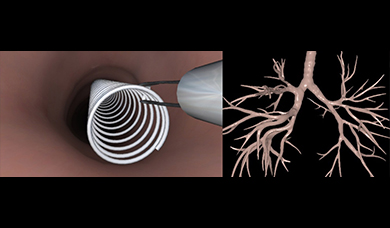

- Includes Essential Bronchoscopy skill tasks module co-developed with AABIP

- Includes CHEST standardized curriculum for essential bronchoscopy skills and diagnostic bronchoscopy, a highly structured training module, co-developed with American College of Chest Physicians

The endobronchial ultrasound assessment tool could be used to provide reliable and valid assessment of competence in EBUS-TBNA, and act as an aid in certification. Virtual-reality simulator training was shown to be more effective than traditional apprenticeship training.

The simulator demonstrated validity in differentiating skill in scope manipulation and airway anatomy, but did not discriminate skill levels in anatomic orientation or identification of lymph nodes. Bronchoscopy simulation was viewed as helpful by all levels and should be considered before performance on patients.